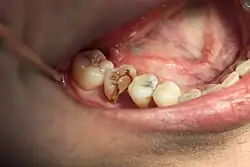

Intraorale Aufnahme der Situation 16 Jahre nach Hemisektion, die 16 Jahre alte Kunststofffüllung ist stark abradiert und insuffizient, weshalb der Zahn nunmehr überkront wurde.